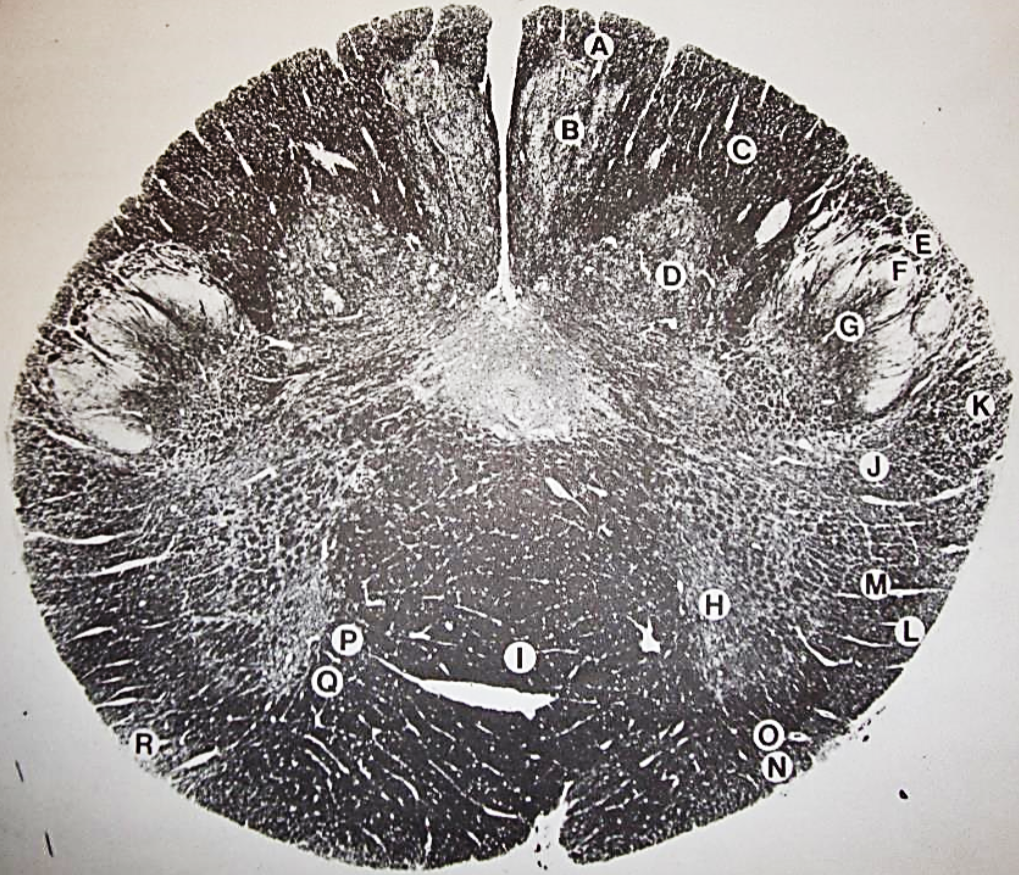

A

Fasciculus gracilis

B

gracile nucleus

C

fasciculus cuneatus

D

cuneate nucleus

E

spinal trigeminal tract

F+G collectively

spinal trigeminal nucleus

H

accessory nucleus

I

pyramidal decussation

J

rubrospinal tract

K

posterior spinocerebellar tract

L

anterior spinocerebellar tract

M

lateral spinothalamic tract

N

anterior spinothalamic tract

O

lateral vestibulospinal tract

P

medial longitudinal fasciculus

Q

tectospinal tract